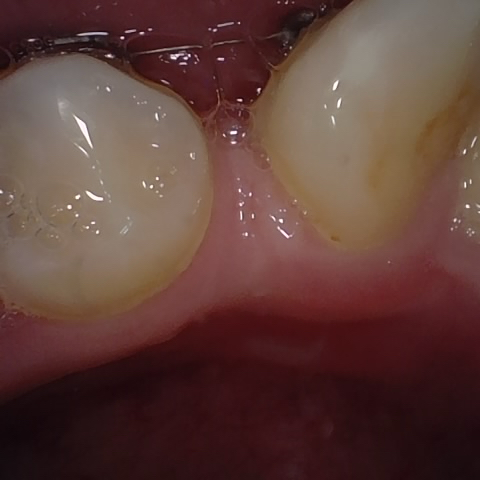

Incorrect Quality Level

The reference annotation for this image is

None

.

Please select the correct quality level.

Annotated as "Bad"